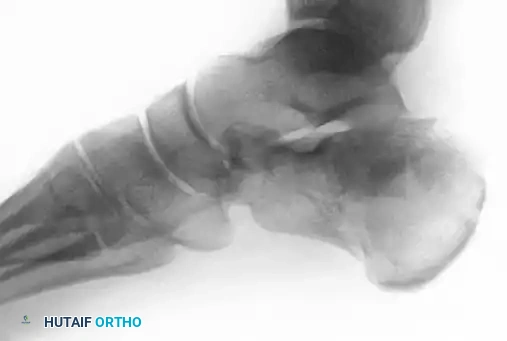

Figure 88-11A: Preoperative radiograph demonstrating a displaced intra-articular calcaneal fracture. Medial and lateral incisions were chosen in this patient due to a significant smoking history and compromised soft tissue envelope.